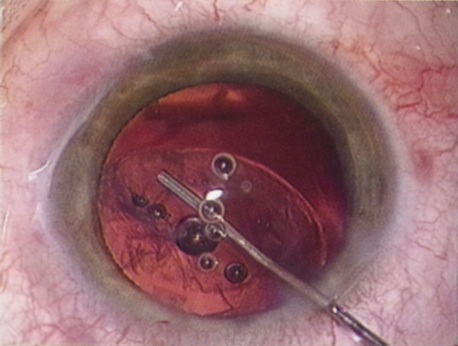

HYDRODISSECTION

Hydrodissection can be performed after the surgeon has successfully completed capsulorrhexis.97 If the capsulorrhexis is not intact, fluid forced around the interior of the capsule may cause the bag to splay open. With capsulorrhexis, hydrodissection is a safe and extremely useful maneuver. Hydrodissection can be thought of as two maneuvers: hydrodelineation and cortical cleaving hydrodissection. By placing a 27-gauge cannula on a syringe filled with balanced saline solution (BSS), the surgeon can direct fluid beneath the residual anterior capsular rim to create a cleavage plane. Depending on the direction the fluid wave takes, different lamellae of the cataract will be separated. Hydrodelineation is the term used when the cleavage plane separates the adult nucleus from the fetal nucleus or the adult nucleus from the more peripheral epinucleus. Hydrodelineation often results in the characteristic golden ring sign (Fig. 11). Cortical cleavage occurs when the cortex is separated from the capsular bag (Fig. 12). Finding the cortical cleavage plane may be facilitated by gently lifting the capsular margin away from the cortex with the BSS cannula before injecting. Several small bursts of fluid allow the surgeon to monitor progress of the fluid wave. When dealing with a soft nucleus, the authors strive to perform true cortical cleaving hydrodissection. For a hard nucleus, hydrodelineation allows manipulation of less of the nuclear bulk, although the remaining epinuclear shell must be addressed in an additional step. Hydrodelineation is particularly useful if the nucleus is not freely mobile after cortical cleaving hydrodissection.

Fig. 11. A crisp “golden ring” is seen from the fluid cleft between the epinucleus and nucleus with hydrodelineation.